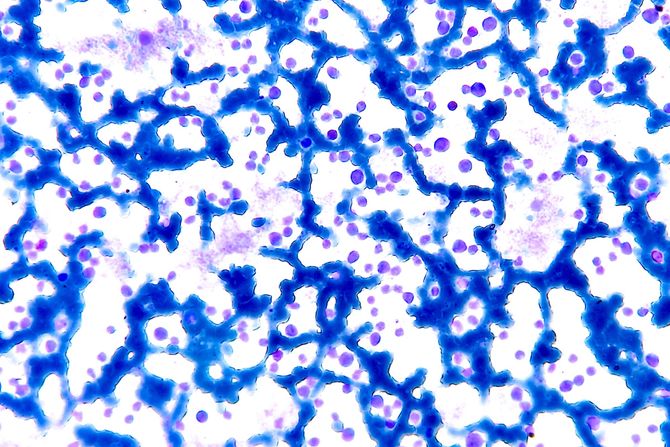

Sve krvne ćelije potiču od matičnih ćelija u koštanoj srži. Koštana srž proizvodi dve osnovne vrste matičnih ćelija: mijeloidne i limfoidne. Limfoidne matične ćelije postaju bela krvna zrnca koja pomažu u borbi protiv infekcija. Mijeloidne matične ćelije mogu da postanu crvena krvna zrnca (koja prenose kiseonik), bela krvna zrnca ili trombociti (koji sprečavaju prekomerno krvarenje).

Matične ćelije dobijaju „uputstva“ od gena koji određuju njihov razvoj i funkciju. Kada dođe do mutacija gena, ćelije praktično dobijaju pogrešna uputstva i nastavljaju da se nekontrolisano dele. Vremenom se nagomilavaju u koštanoj srži ili krvotoku, ometajući normalan protok krvi. Ovakva blokada može da dovede do ozbiljnih zdravstvenih problema.

Dijagnoza se postavlja na osnovu kompletne krvne slike, razmaza periferne krvi, biopsije koštane srži i genetskog testiranja.